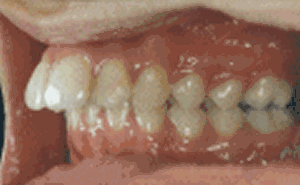

其实“龅牙”是东方人种中较为常见的一类牙颌面畸形,在医学专业上实质是上颌前突畸形或双颌前突畸形,一般不伴有严重的功能障碍,但非常影响美观,患者求治的目的主要是为了改善容貌。寇主任说,现在不用再为自己的龅牙苦恼啦,成人龅牙完全可以通过美容冠进行修复。

龅牙是较为常见的一类牙颌面畸形,龅牙非常影响美观,很多成人朋友希望通过龅牙矫正来改善他们的容貌、牙齿咬合状况,能够拥有灿烂的微笑。但是龅牙美容冠的矫正方法在不同的年龄阶段可以采用不同的方式:

未成年人做龅牙的矫正方法:对于未成年人采用正畸矫正(带牙套)较好,较佳的矫正期一般是11-14岁。通过力学的拉动可以使牙齿恢复整齐。

美容冠的矫正龅牙是一种目前流行于欧美日韩的新兴牙齿美容技术,该技术在传统烤瓷牙的基础上强调牙齿的美容效果,针对成人错位牙、畸形牙的临床冠部分施以专业手段,较后用美容冠加以修复。具有美牙不拔牙,无痛苦,时间短,牙齿坚固,多年后牙龈不会出现黑线等优点,从而达到终生有保障的美牙效果。